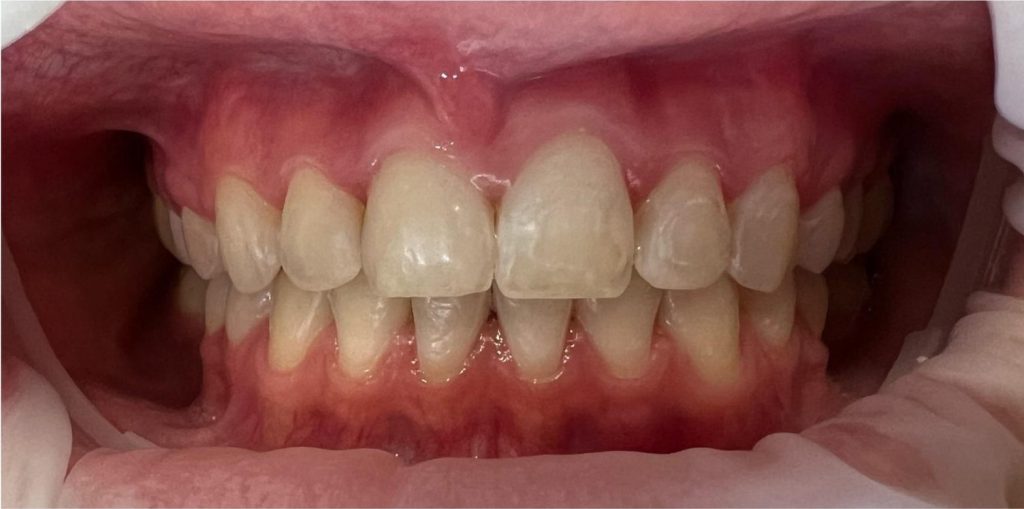

Pod opieką Agnieszki Łukowicz, Master of Science Orthodontics została poddana zaawansowanemu leczeniu aparatem stałym ligaturowym, Dzięki czemu udało się osiągnąć znaczące zmiany:

poszerzenie luków zębowych,

korekta tyłozgryzu,

rozwiązanie stłoczenia,

odrotowanie zrotowanych zębów,

odbudowa startych zębów.

Efekt estetyczny został dopełniony przez wybielanie zębów i odbudowę kompozytową wykonaną przez dr Monikę Niewitecką.

Przedstawiamy piękny i zdrowy uśmiech naszej Pacjentki!